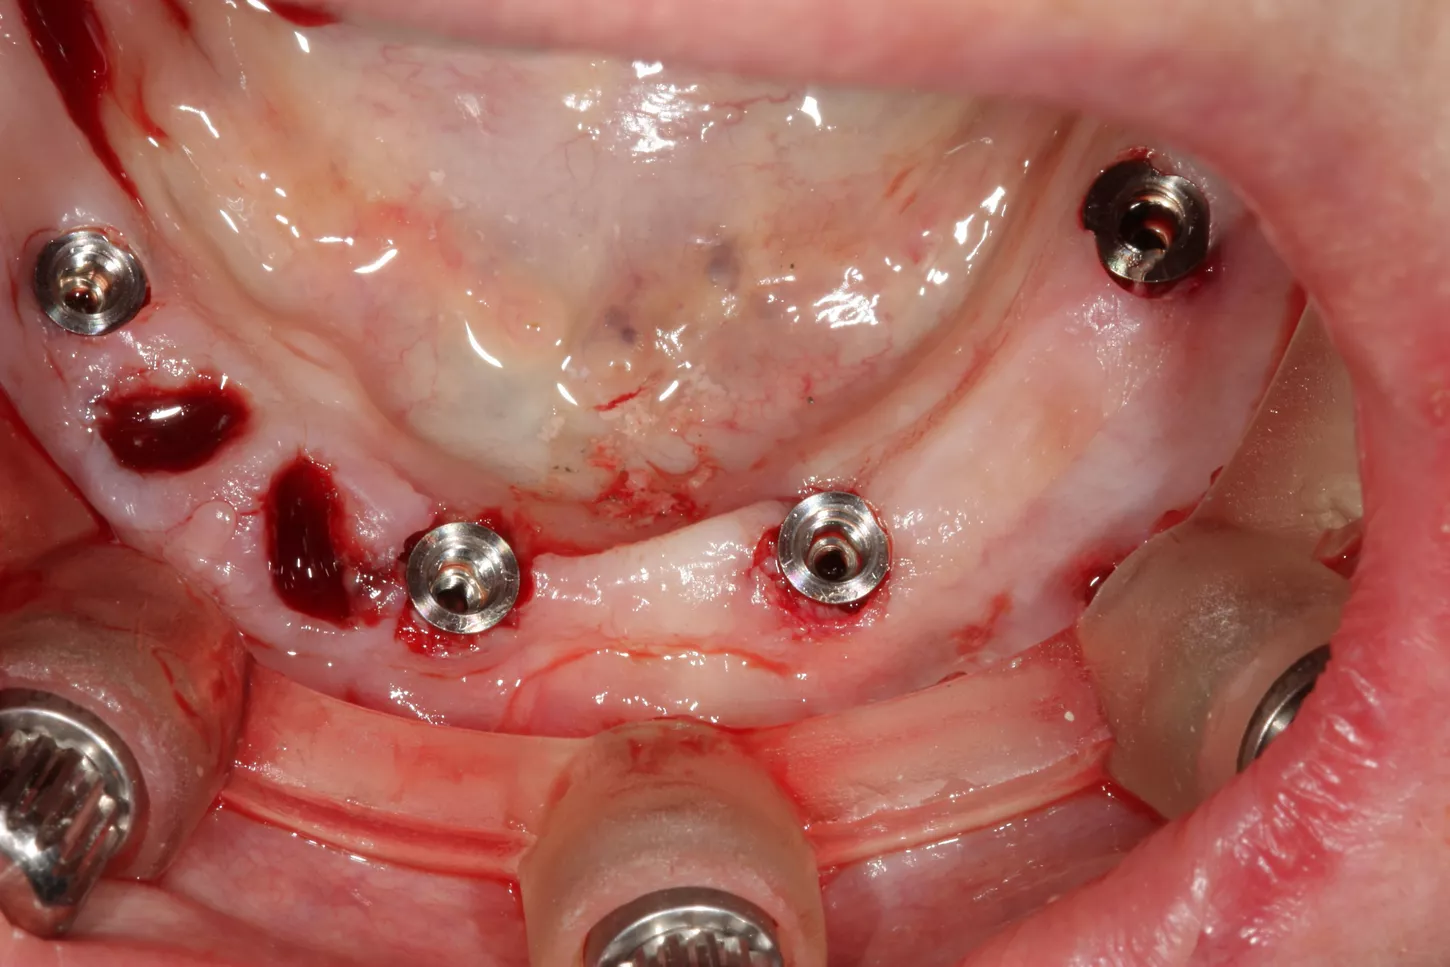

13. Occlusal pictures of healing around the implants at 3 months follow-up upon removal of the provisional prosthesis.

14. Positioning of the transfers in the lower jaw for impression.